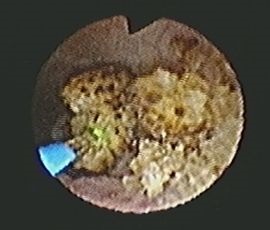

[尿管結石] 手術:経尿道的尿路結石破砕術(TUL)

手術画像